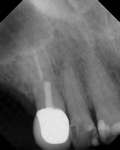

Figure 3D The site 6 months after surgery, confirming integration. Figure 4A Preoperative radiograph showing ridge resorption.

Figure 4B Radiographic confirmation of graft confinement and incremental addition.

Figure 4C Radiographic view of implant placed simultaneously with sinus bone grafting in site No. 3. Figure 4D Radiographic confirmation of the re-establishment of the sinus floor. Figure 4E Final implant-supported restoration.